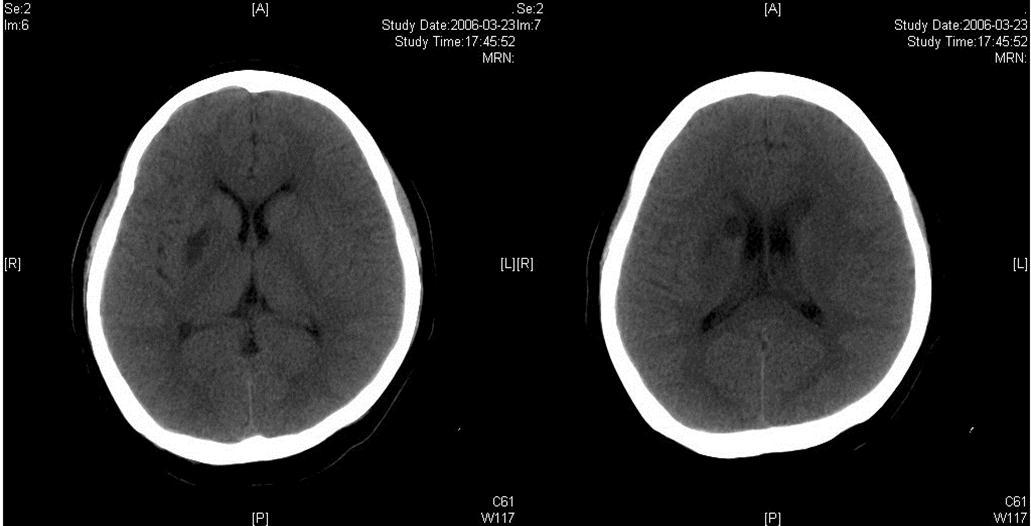

The same dose of aspirin, clopidogrel and subcutaneous LMWH was used after the operation. Two days after the stenting (Mar 23), three successive bouts of left limb weakness along with slight dizziness occurred, lasting about 10 minutes with intervals of 30 minutes. There were no abnormal signs between the first and second attacks. Babinski sign was noted during the second attack and persisted in the left between the second and third attacks with normal muscle strength, but she felt weakness. Blood pressure was 140/70 mmHg. After the third attack, her tongue deviated slightly to the left side. There was slight decrease in muscle strength and Babinski sign was positive in the left. Emergent CT displayed two low density lesions with clear edge and homogeneous density in the right basal ganglia (Figure 3). Aspirin 300mg was given emergently. Compared with the Transcranial Doppler (TCD) test before the operation (March 3), emergent TCD showed the blood flow velocity increased significantly in both anterior cerebral artery (ACA), especially in right ACA (Table 1). She got partial recovery after being given volume expansion treatment with low molecular dextran. Then she was given anticoagulant treatment with intravenous unfractionated heparin (UFH) (500 U/h). LMWH was stopped. On the next day, her muscle strength recovered to normal, but pathological sign persisted. Anticoagulation therapy was continued along with dual antiplatelet therapy. On Mar 25, limb weakness appeared again, muscle strength was Ⅳ grade in the left, both Babinski sign and Chaddock sign were positive. Volume expansion with low molecular dextran was ineffective, and the dose of UFH was increased to750 U/h. Two days later, muscle strength and plantar reflex recovered to normal. On Mar 27, CT scan revealed that the lesion did not change compared with the previous scan, and there was no new lesion. Dose of UFH was reduced to 500H/h. During treatment, blood coagulation test was performed for several times, PT was stabled at 14.1~15.5 sec, APTT at 32.7~43.1 sec, INR at 66.6%~78.8%, activity of antithrombin Ⅲ (AT Ⅲ) at 70.4%~97.2%, and fibrinogen at 3.93~4.68 g/L. UFH was replaced by LMWH on Mar 31. CTA (Apr 3) displayed the stent was in M1 segment of right MCA, its proximal lumen was attenuated compared with the left MCA, with slightly compromised distal blood flow (Figure 4).

Figure 3.Two infarcts displayed in CT images

The right MCA stenosis, which led to the transient ischemic attack (TIA) symptoms, was definitely diagnosed. Angioplasty and stenting was conducted after full preparation of dual anti-platelet therapy. Immediately before the operation, LMWH was used in combination and was continued after operation. Her condition was stable in the first two days after operation. Then crescendo TIA recurred and led to motor impairment. Two lesions were shown in the emergent CT images. One was near the anterior horn of the right lateral ventricle, by which it was difficult to explain the symptoms and physical signs. The other was in basal ganglia, and was related to the symptoms and signs. The signal in this region had been slightly higher than the counterpart in the left in the source image of MRA before operation. Hence the lesion in basal ganglia was thought to result from hemodynamic impairment in distal parts of stenotic MCA. Both lesions had clear boundaries, which indicated that the infarction in the area supplied by deep branch of MCA occurred before the TIA attacks. The crescendo TIA worsened gradually, but got partial recovery after volume expansion treatment initially. TCD test showed the blood flow velocity increased in both ACA, especially in the right, while that in the right MCA did not significantly increase. This indicated that some collateral circulation had formed, to counteract hypoperfusion caused by progressive stenosis in the right MCA. Based on these, we deduced that there was IST which did not completely block the right MCA. The symptoms and physical signs appeared again when there was failure of collateral compensation. Because there were new lesions on CT scan and the patient had been treated with dual anti-platelet treatment and anticoagulation, thrombolytic therapy could not be given. So we gave unfractionated heparin (UFH). The symptoms and physical signs disappeared on the next day. But two days later during the same treatment, the symptoms and signs recurred, volume expansion was ineffective, this indicated that initial recovery of symptoms was due to compensatory collateral circulation, and anticoagulation therapy with UFH may also play a role. But this could not prevent thrombosis from progressing, so we increased the dose of anticoagulation drugs, the symptoms and signs disappeared eventually. CTA (Apr 3) and repeated TCD (Apr 17) confirmed our reasoning with attenuated proximal lumen of right MCA and increased blood flow velocities of the right MCA and ICA.